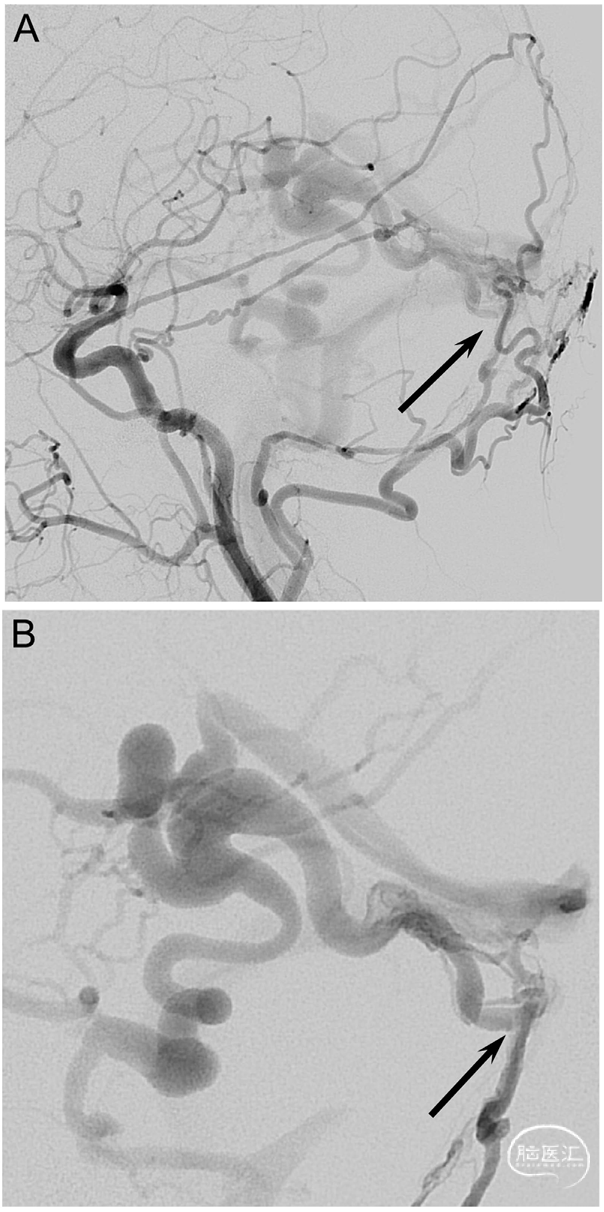

Fig. 1. A 52-year-old woman (patient no. 3) with headache and pulsatile tinnitus underwent an MRI showing dilated veins in the posterior fossa. A diagnostic DSA confirmed a high-grade tentorial DAVF near the confluence (Borden type III, Cognard type IV). A.-B. Left CCA and left selective posterior meningeal artery (PMA) injections in lateral views show a DAVF (arrow) with deep venous drainage and several venous ectasias. C. Lateral view showing the transfistulous approach performed via the left PMA using a triaxial system with a 5F Sofia and a 1.3F Headway™ Duo (Terumo Neuro) reaching the proximal venous outflow (arrow). D.-E. Roadmap in lateral views. The fistulous outflow consisted of two adjacent, first separately draining and then merging veins, both of which were tightly packed with coils (arrows). Due to the high flow, the 2nd and more enlarged distal portion (E) required an oversized HydroCoil18 (10 mm x 31 cm, Terumo Neuro) for a stable basket to be filled with smaller Target XL coils (Stryker). F. Late-phase left ICA control run in lateral view shows formation of thrombus in the dilated draining vein as a filling defect (arrow). G. Left occipital artery control run in lateral view shows complete occlusion of the arteriovenous shunting. Follow-up DSAs showed near-complete occlusion after 3 months and complete occlusion after 9 months (not shown).